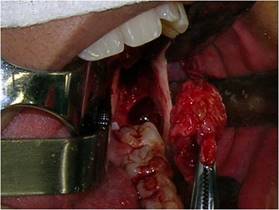

Bajo anestesia general, intubación nasotraqueal, tras antisepsia extra e intrabucal con solución de clorhexidina al 2 y al 0,12 %, respectivamente, se realizó la colocación del campo operatorio y el taponamiento del cruce orofaríngeo con "packing". Luego, se realizó una infiltración subperióstica a nivel de la región del trígono retromolar, donde había fluctuación por erosión cortical, con solución de clorhidrato de bupivacaína al 0,5 % con hemitartrato de epinefrina 1:200.000 para promover la hidrodisección perióstica y hemostasia. A continuación, se realizó la aspiración con una jeringa tipo luer de 10 cm³ con aguja 40X12 y se recolectó líquido seropurulento en cantidad abundante (Fig. 3).

En secuencia, se realizó una incisión circunferencial con un mango para bisturí n.º 3 equipado con una lámina 15, lo suficientemente profunda para penetrar al interior de la lesión. Además de extraer este tejido, también se extrajo un fragmento de la cápsula de la lesión por separado, con el fin de obtener una muestra más específica de la lesión (Fig. 4).

Todo el material extraído se fijó inmediatamente en una solución de formol al 10 %. Se realizó una sutura de puntos aislados en toda la zona resecada, abarcando la cápsula de la lesión y la mucosa circundante (Fig. 5). Después de la toilette de la cavidad con suero fisiológico, la cavidad restante se tamponó con una gasa con medicamento impregnada en sulfato de neomicina 5 mg/g y bacitracina zinc 250 UI pomada.